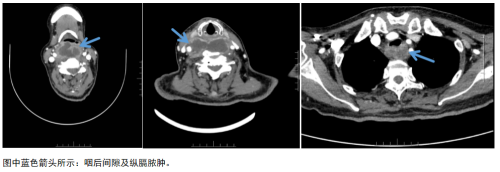

送至医院时,患者情况已十分危急,经检查确诊为咽后间隙脓肿伴纵隔脓肿形成,炎症紧邻气道及颈部大血管,随时可能引发气道梗阻、脓毒血症、大出血等致命并发症。急查相关检验指标,患者血糖已高达31mmol/L,并发严重的酮症酸中毒。

医院多学科协作,各个环节紧密相连,一路绿通:放射科完善颈、胸部增强CT联扫,精准评估了病变范围;肾病内分泌科指导降糖、消酮用药方案;在麻醉手术科全程保驾护航之下,耳鼻咽喉头颈外科完成颈部切开入路咽后及纵隔脓肿引流术;急诊手术后,ICU接手给予强效抗感染、纠正酸中毒等综合治疗。经过医护团队的严密监护与精细化救治,患者生命体征平稳后转回耳鼻咽喉头颈外科普通病房继续康复。